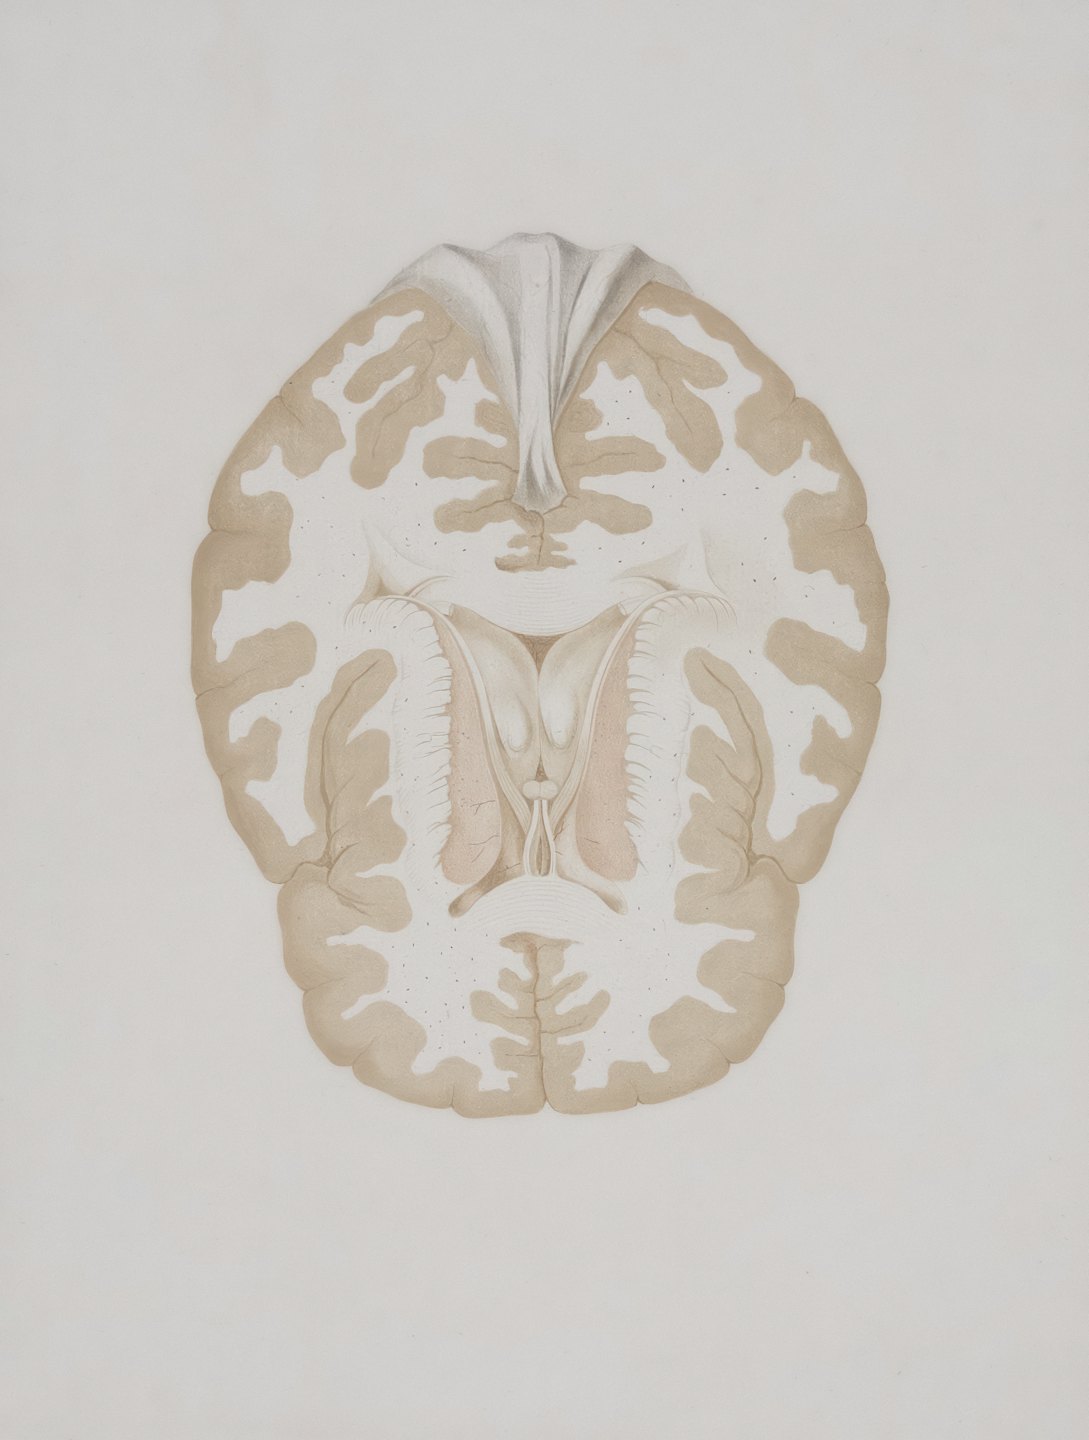

Pioneering Cognitive Exploration

Delve into revolutionary research that unlocks new understanding of human thought and decision-making.